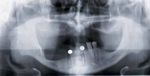

Fig. 2   Relation intermaxillaire du même patient avant la pose des implants.   Fig. 3 Relation intermaxillaire du même patient avant la pose des implants

après réduction de la crête osseuse et implantations dans le maxillaire inférieur.

quées plus haut, on se trouve apparemment dans une relation

intermaxillaire sagittale de Classe III. Le montage des dents

dans un maxillaire supérieur avec une crête flottante sera sans

doute difficile, ce d’autant qu’il s’agit de trouver un équilibre

favorable entre les critères esthétiques et les facteurs influen-

çant la stabilité de la prothèse. L’avulsion des dents antérieures

mandibulaires et la réduction de la crête alvéolaire élargissent

considérablement la marge de manœuvre pour la réalisation

du nouveau plan d’occlusion. La configuration intermaxillaire

ainsi créée dans les segments antérieurs est la clé d’un montage

adéquat des dents antérieures dans le maxillaire supérieur (fig. 2

et 3).